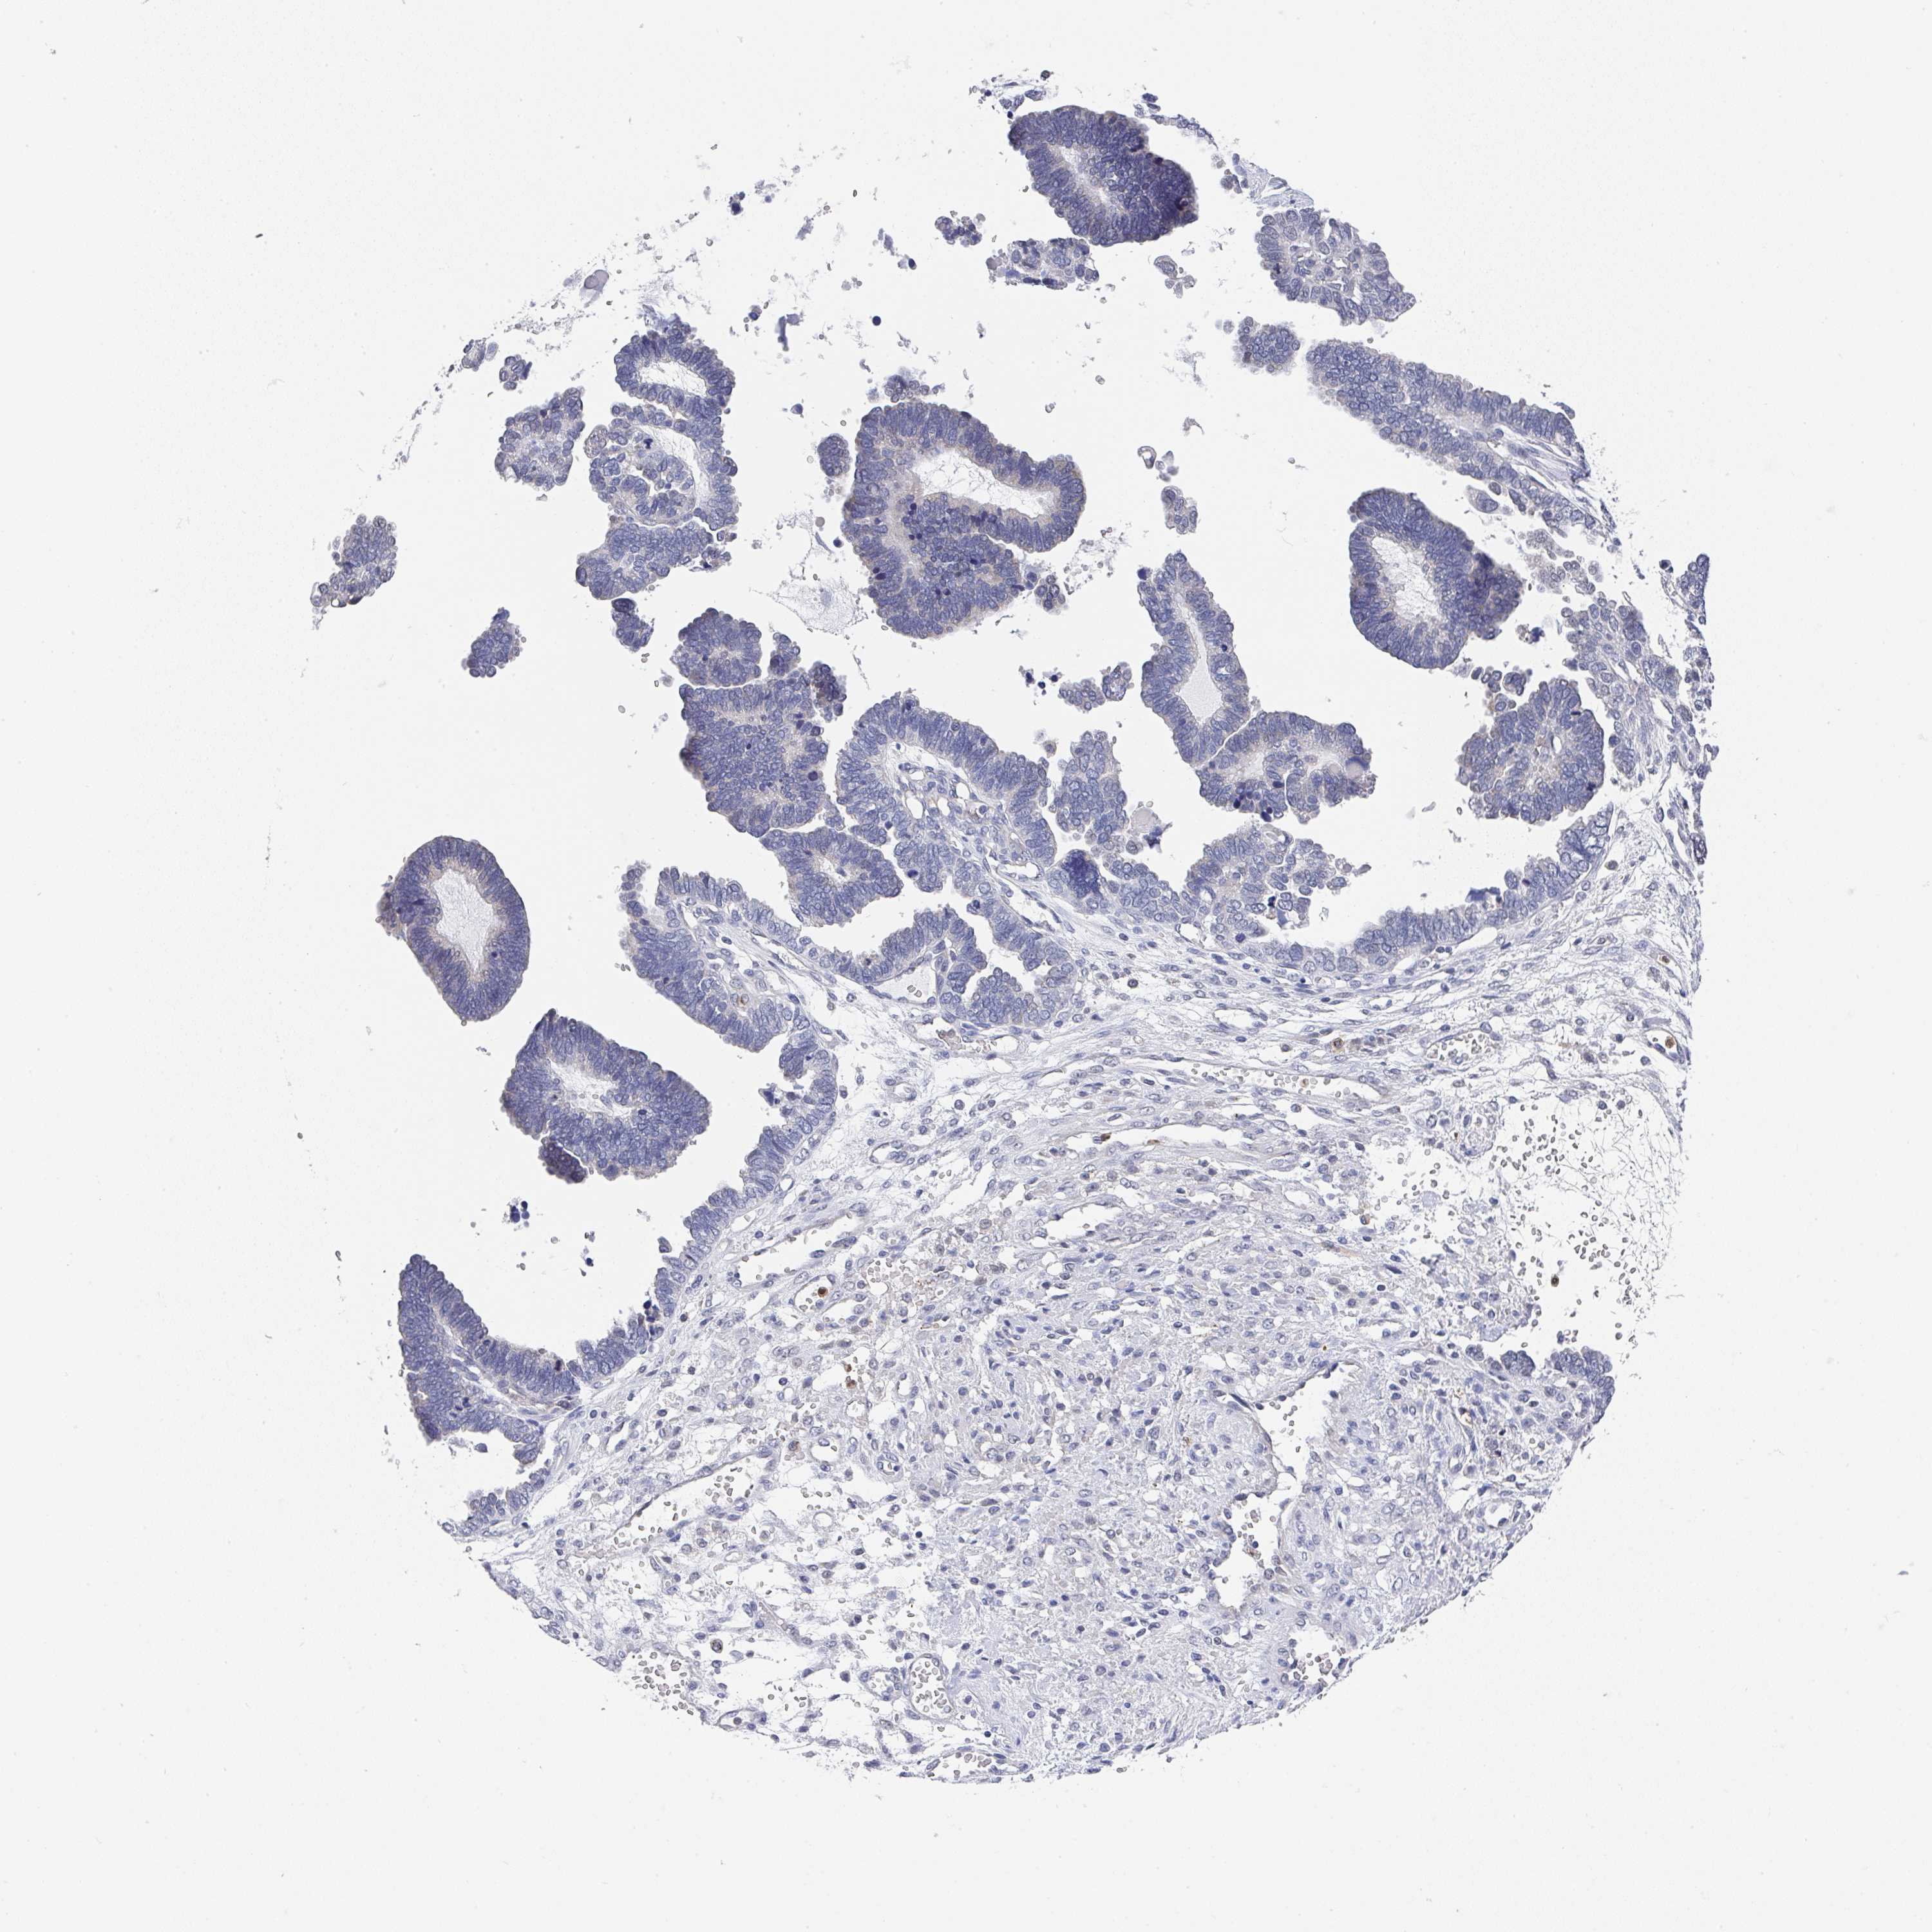

OVARIAN CANCER - Protein expressioni

A mouse-over function shows sample information and annotation data. Click on an image to view it in a full screen mode. Samples can be filtered based on level of antibody staining by selecting one or several of the following categories: high, medium, low and not detected. The assay and annotation is described here.

Note that samples used for immunohistochemistry by the Human Protein Atlas do not correspond to samples in the TCGA dataset.

Antibody stainingi

Antibody staining in the annotated cell types in the current human tissue is reported as not detected, low, medium, or high, based on conventional immunohistochemistry profiling in selected tissues. This score is based on the combination of the staining intensity and fraction of stained cells.

Each image is clickable and will lead to virtual microscopy that enables deeper exploration of all samples and also displays staining intensity scores, fraction scores and subcellular localization as well as patient and tissue information for each sample.

Antibody HPA047836

Antibody HPA052095

Antibody CAB004524

Staining

High

Medium

Low

Not detected

Cystadenocarcinoma, serous, NOS

Cystadenocarcinoma, mucinous, NOS

Carcinoma, endometroid